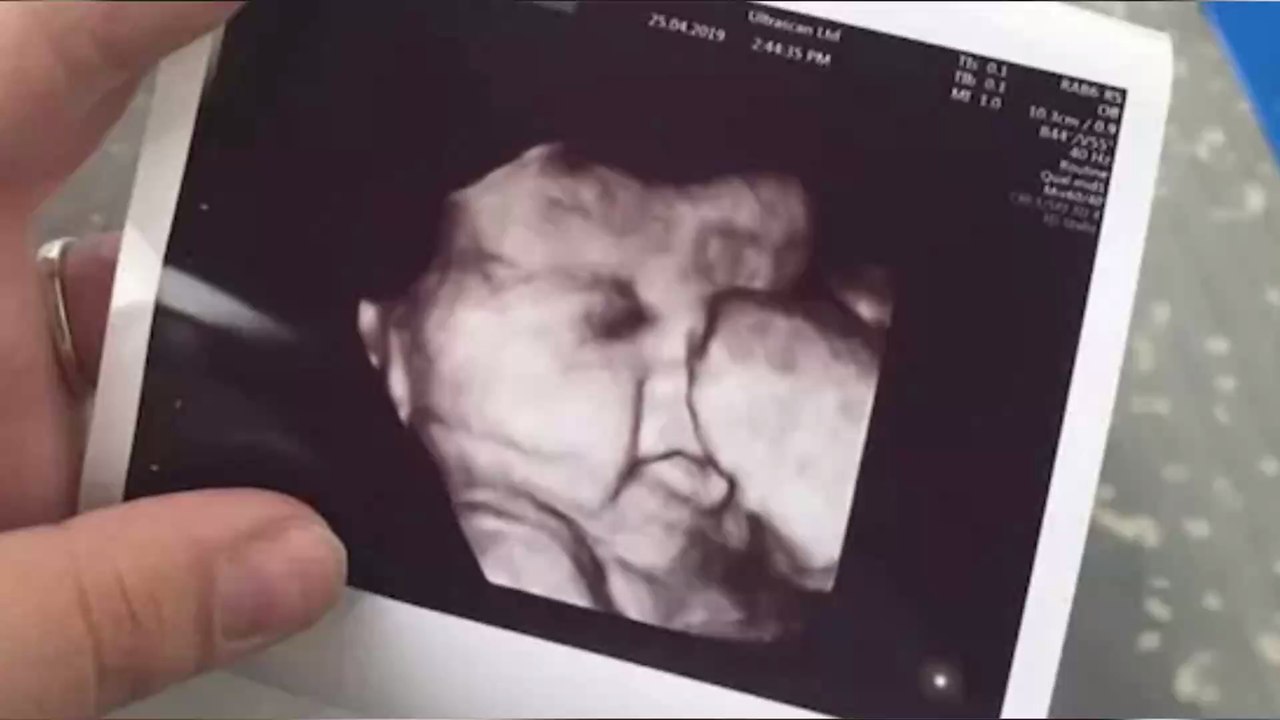

Pregnant Woman Left Astonished When She Saw Her 34 Week Scan 1:06

Pregnant Woman Left Astonished When She Saw Her 34 Week...

OhMyMag UK 20 views